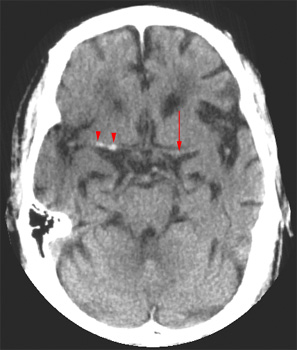

Head CT > Stroke > Hyperdense Vessel

A hyperdense vessel is defined as a vessel denser than its counterpart and denser than any non-calcified vessel of similar size. This is seen in 25% of stroke patients. In patients presenting with clinical deficit referable to the middle cerebral artery territory, the hyperdense vessel sign is present 35-50% of the time. This sign indicates poor outcome and poor response to IV-TPA therapy.